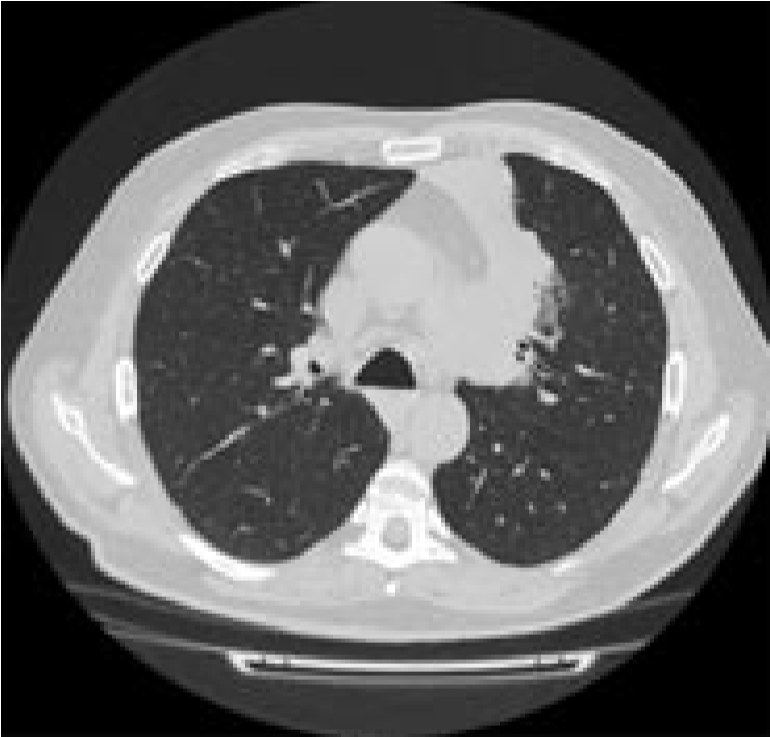

От предложенной по месту жительства эксплоративной операции (торакотомия) пациент отказался и самостоятельно обратился в консультативно-поликлиническое отделение (КПО) ФБГНУ «ЦНИИТ» для уточнения диагноза. При обследовании в КПО реакция на пробу Манту с 2ТЕ ППД-Л через 72 ч – отрицательная, реакция на пробу с АТР (антиген туберкулезный рекомбинантный) через 72 ч – отрицательная. Клинический анализ крови и мочи – без особенностей. По данным КТ ОГК от 22.08.2017 г., у пациента выявлены сочетанная аденопатия средостения, преимущественно с поражением групп лимфоузлов 2R, 4R, 7, 4L, а также дистелектаз S1-2 и S3 левого легкого, связанный с аденопатией (рис. 1)2

Рис. 1. Аксиальные срезы компьютерной томограммы в легочном (а) и средостенном (б) режимах пациента А.